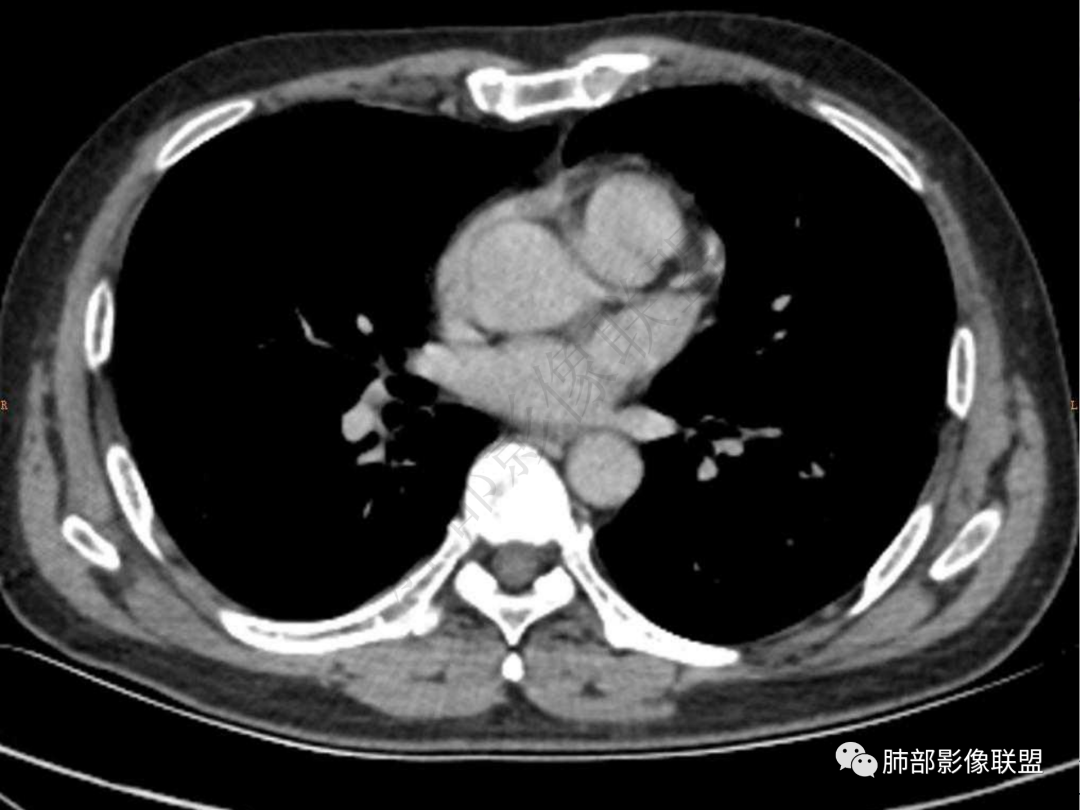

4.实性部分不均匀环形强化并显示一小范围低密度坏死区或空洞。较之肺窗,整体纵隔窗范围较小,提示病灶并不十分密实。抑或为不同时段图像。

5.双肺门及纵隔未见增大淋巴结。未见胸腔积液。

肺脓肿:环形强化,强化较显著。如出现明显囊壁样强化甚至边缘“憩室”样突出,高度支持肺脓肿。